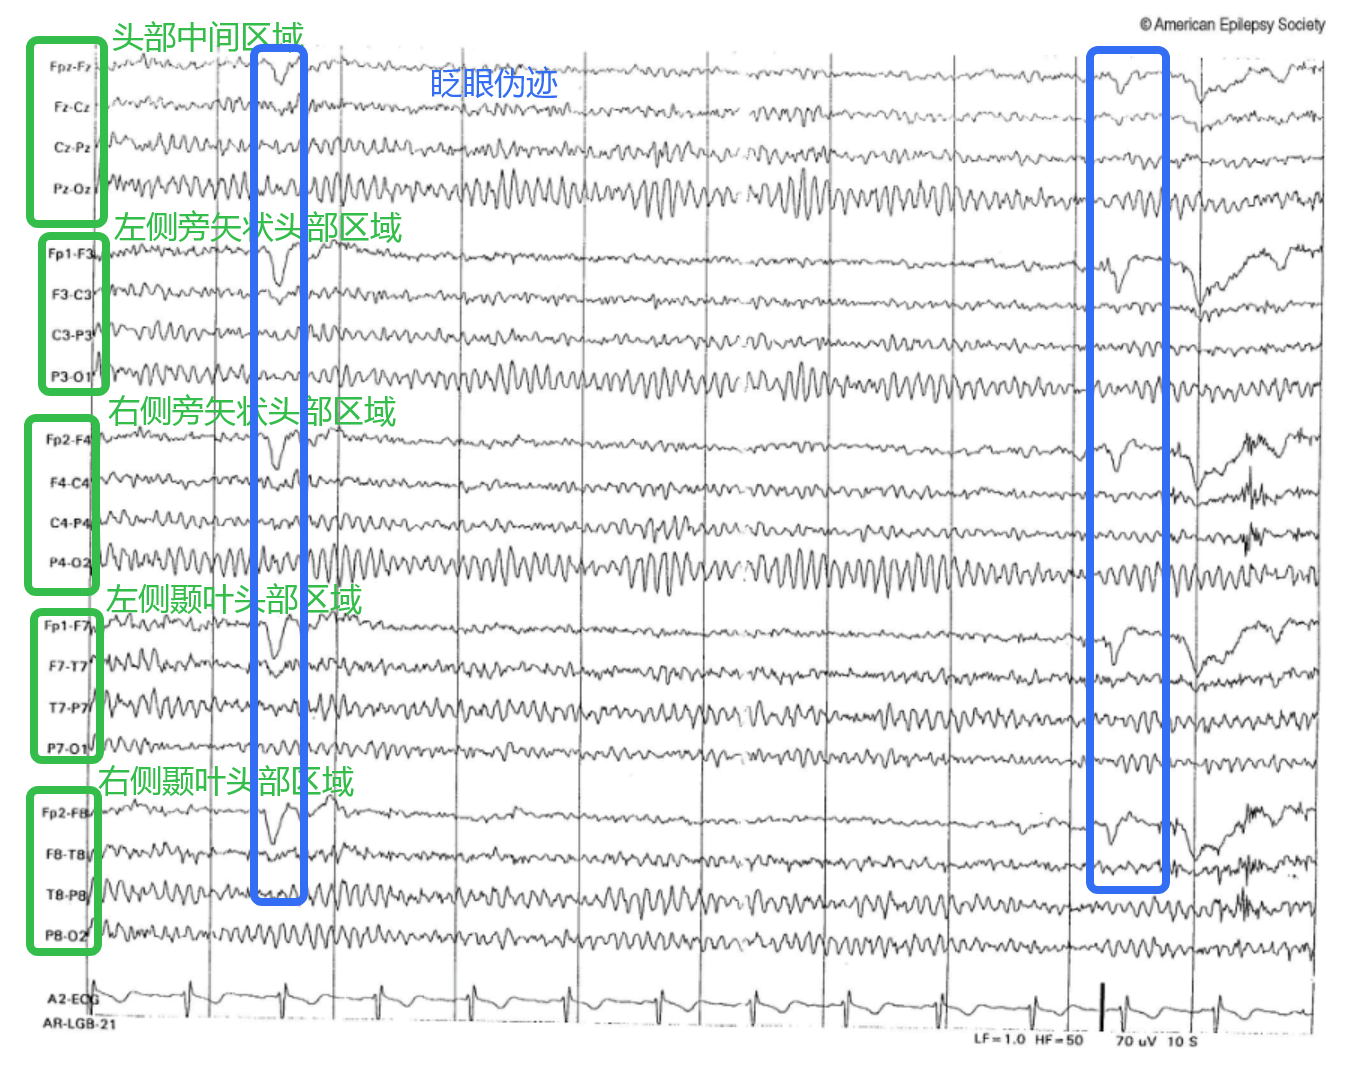

3. 常见蒙太奇

蒙太奇:对 EEG 通道进行标准化排列和选择的方式。

• 双极蒙太奇:每个通道记录相邻电极之间的电位差。(纵向双极、横向双极)

• 参考蒙太奇:每个记录点极与一个远处参考电极比较。

• 拉普拉斯蒙太奇:每个活动电极与周围电极的加权平均值

5. 后部主导节奏

占主导地位的α节律为特征(α波振幅通常左右对称;睁眼或注意力集中时,α节律振幅衰减甚至完全消失)

在这里插入图片描述

6. 不同步节律:

在健康成年人中,脑电图(EEG)表现出低振幅、混合频率的背景节律,也称为不同步节律。

(1)α节律:振幅适中,频率 8–13 Hz,α波振幅左右对称